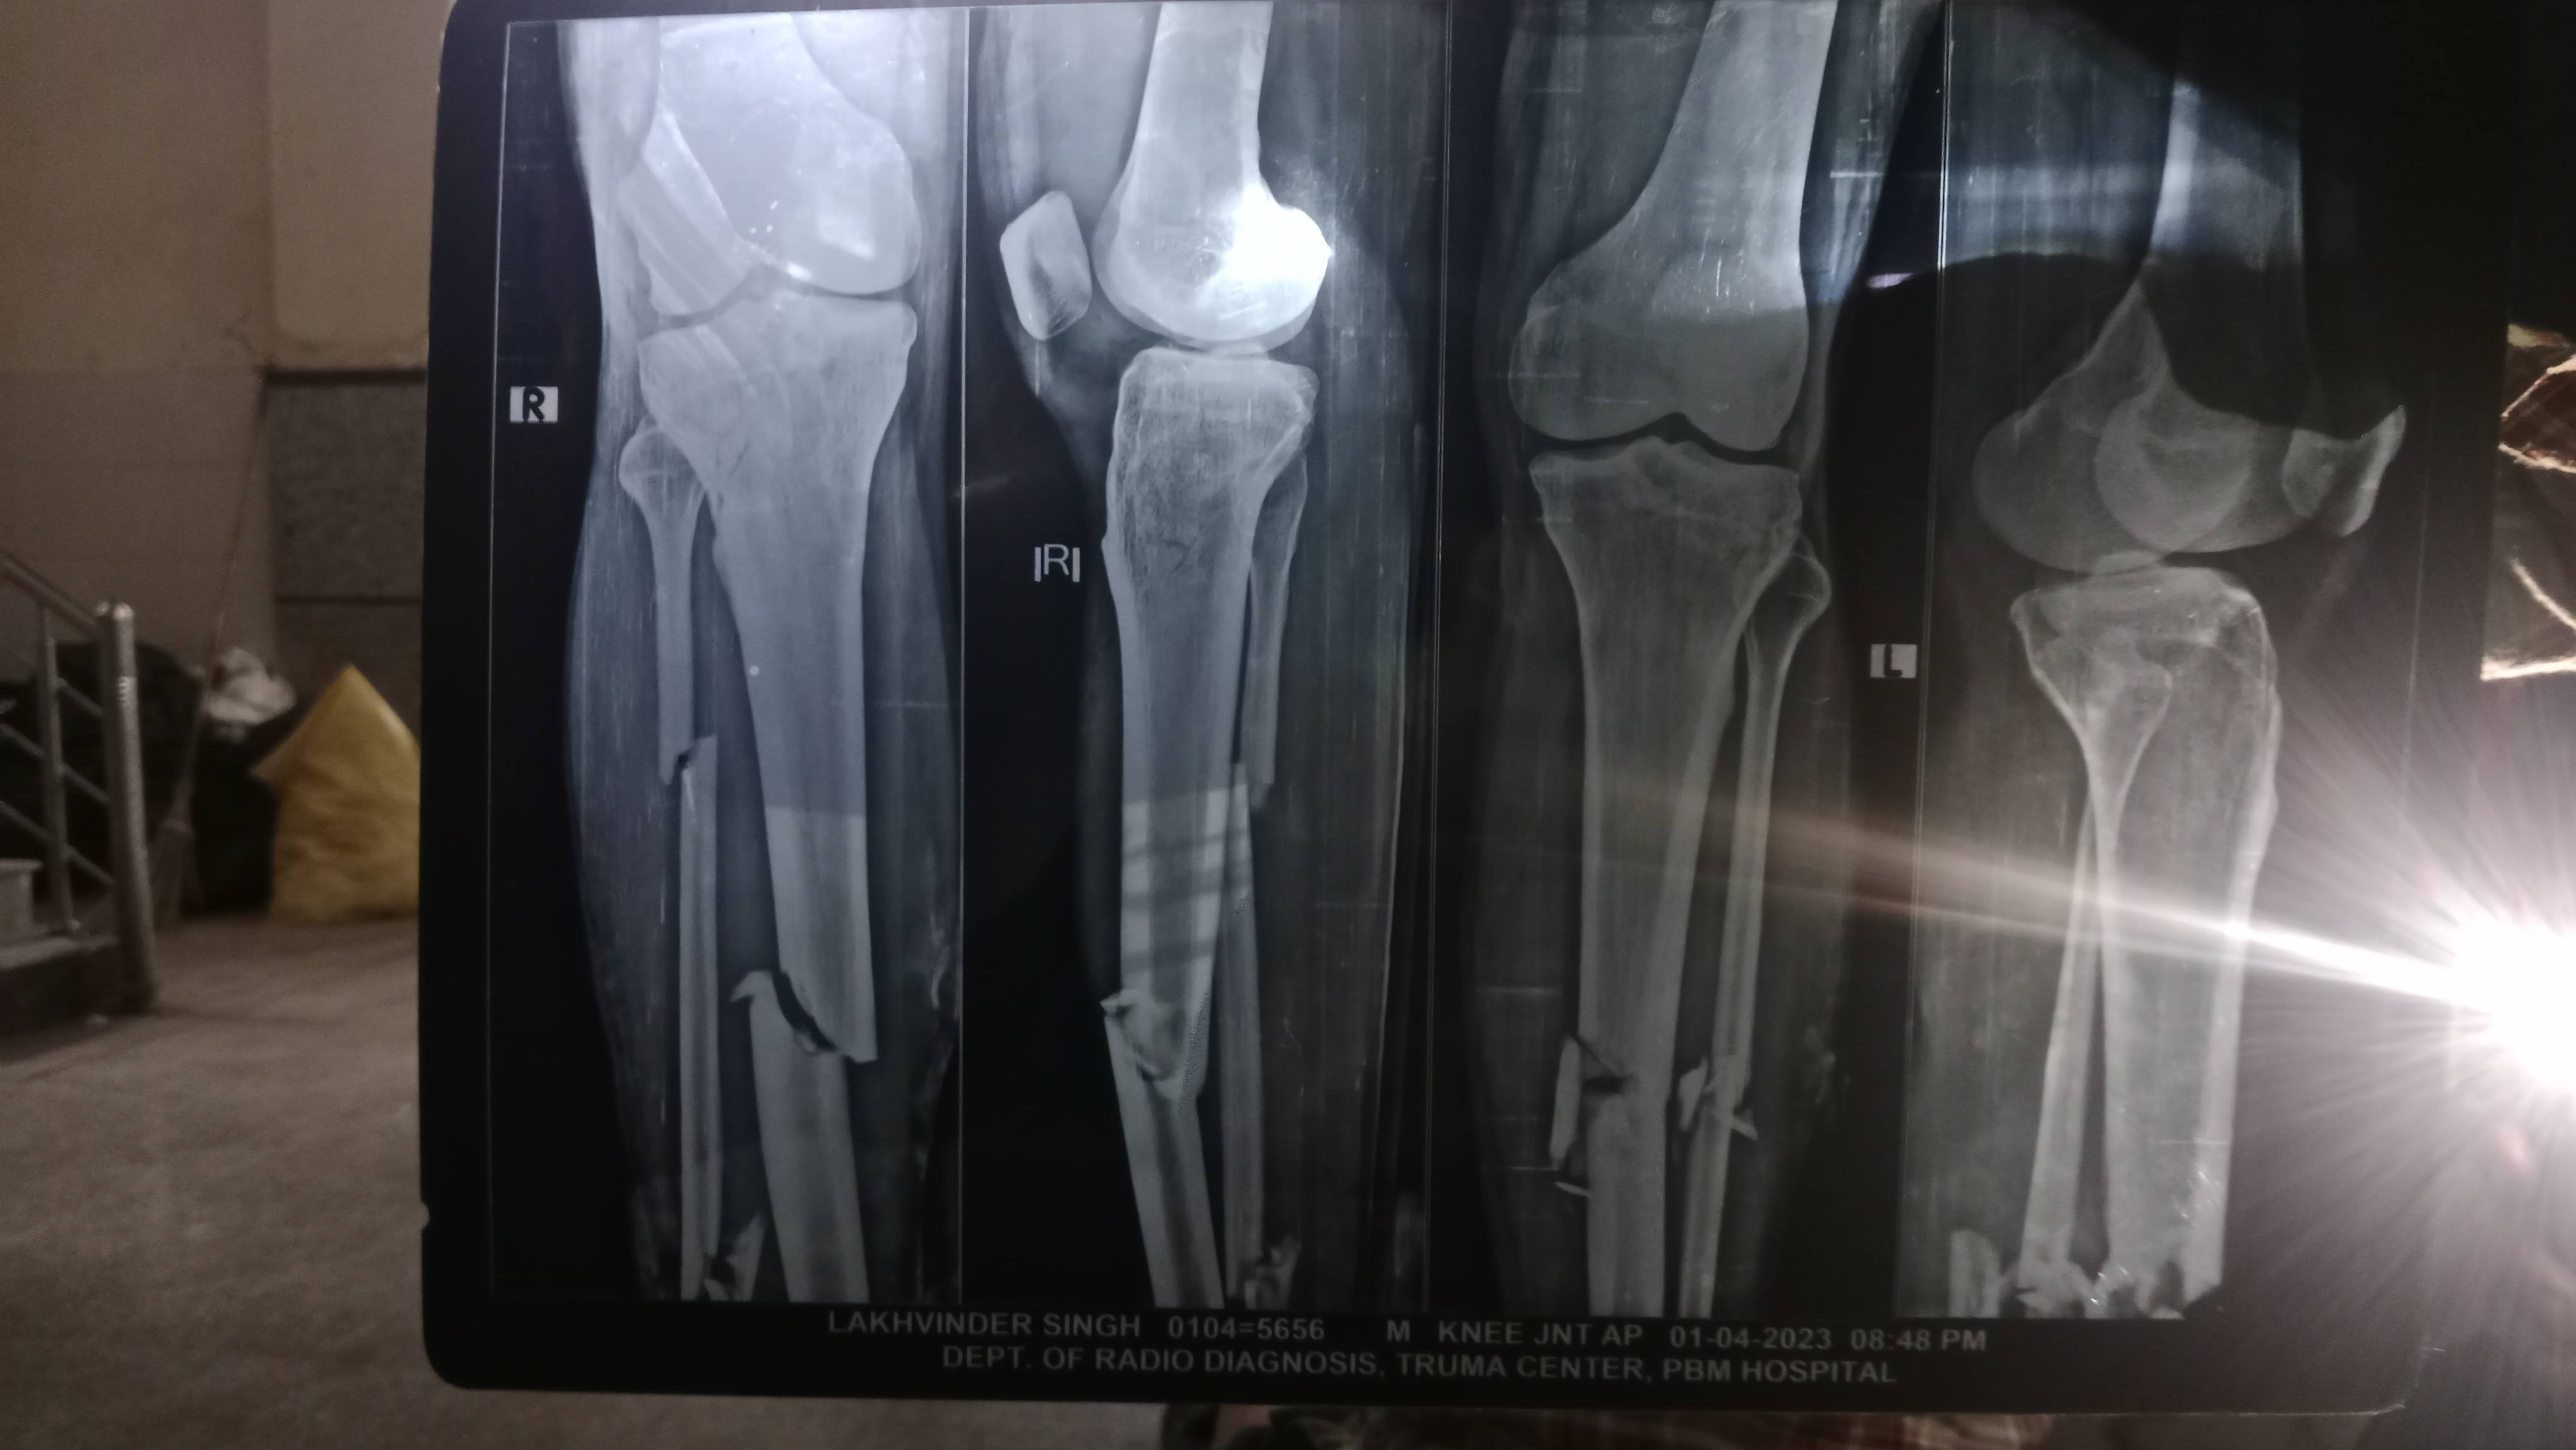

X_ Ray hai clavicle bone ka